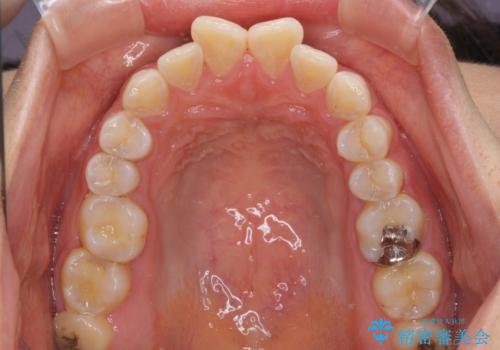

前歯の捻れを改善 インビザラインによる矯正治療

- 前歯の翼状捻転を気にして来院された患者様です。

全体的に叢生は軽度であったため、インビザラインにて矯正治療を行うこととしました。

前歯の幅の大きさも気になっていたため、IPRにより叢生を解消するとともに、歯の大きさも改善しました。